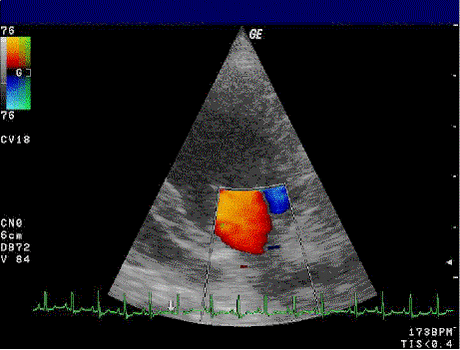

Основано на кодировании в цвете значения доплеровского сдвига излучаемой частоты. Методика обеспечивает прямую визуализацию потоков крови в сердце и в относительно крупных сосудах. Красный цвет соответствует потоку, идущему в сторону датчика, синий — от датчика. Темные оттенки этих цветов соответствуют низким скоростям, светлые оттенки — высоким. Недостаток: невозможность получения изображения мелких кровеносных сосудов с маленькой скоростью кровотока. Достоинства: позволяет оценивать как морфологическое состояние сосудов, так и состояние кровотока по ним.

- Color doppler (CFM или CFA) — цветовой доплер (Color Doppler) — выделение на эхограмме цветом (цветное картирование) характера кровотока в области интереса. Кровоток к датчику принято картировать красным цветом, от датчика — синим цветом. Турбулентный кровоток картируется сине-зелено-желтым цветом. Цветовой доплер применяется для исследования кровотока в сосудах, в эхокардиографии. Другие названия технологии — цветное доплеровское картирование (ЦДК), color flow mapping (CFM) и color flow angiography (CFA). Обычно с помощью цветового доплера, меняя положение датчика, находят область интереса (сосуд), затем для количественной оценки используют импульсный доплер. Цветовой и энергетический доплер помогают в дифференциации кист и опухолей, поскольку внутреннее содержимое кисты лишено сосудов и, следовательно, никогда не может иметь цветовых локусов.